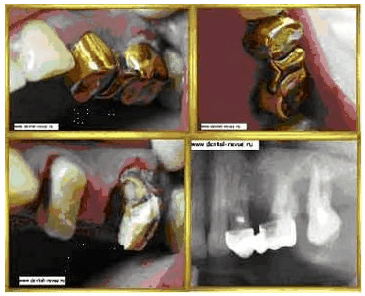

Вид штампованно-паянной конструкции прослужившей своему хозяину 7 лет.